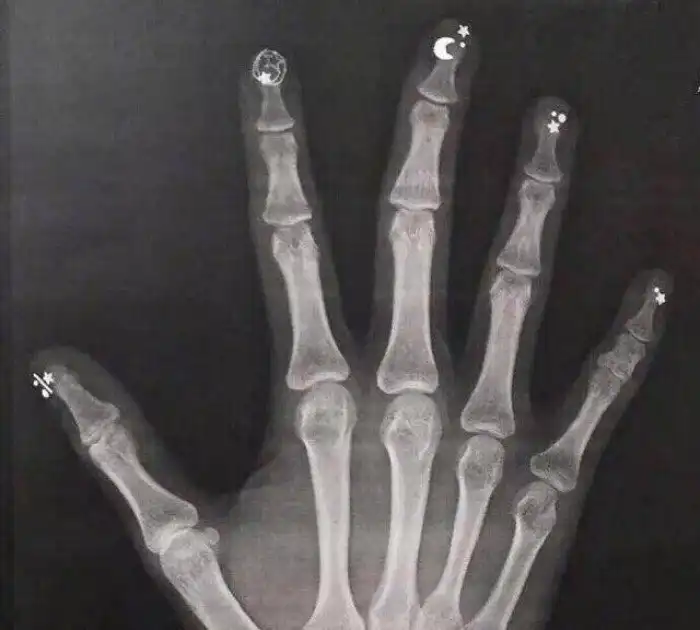

9. Рентген с маникюром